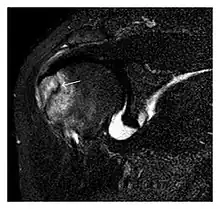

The greater tuberosity of the humerus is also an illustrative location of occult fractures. The osseous injury may follow seizures, glenohumeral dislocation, forced abduction, or direct impaction. They are commonly discovered on MRI in symptomatic patients with suspicion of rotator cuff tear. Coronal images are best suited for detection. They appear as crescentic oblique lines surrounded by a bone marrow edema pattern (Figure 5). The rotator cuff must be inspected since associated ligamentous lesions are common. In the ankle, malleoli and tarsal bones should be checked carefully for any cortical disruptions and radiolucent lines that may reveal a fracture. Awareness of the exact location of the pain will help direct the attention of the interpreter when searching for very subtle signs of fracture (Figure 6).[1]

a

b

Figure 6: Subtle anterior talar fracture in a 39-year-old man presenting with ankle pain after a fall. (a) Anteroposterior radiograph shows a subtle oblique radiolucent line through the talus (white arrows). (b) Sagittal CT reformation confirms the presence of an anterior talar fracture with cortical offset (black arrow). Avulsion fractures, which consist of a detached bone fragment resulting from a ligament or tendon pulling away from the bone, may also present with subtle radiographic signs. Tiny osseous fragments near the presumed attachment site of a ligament suggest this diagnosis. Common sites are the lateral tibial plateau (the Segond fracture), the spinal tuberosity of the tibia resulting from anterior cruciate ligament avulsion, and the ischial tuberosity.[1]